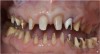

Figure 8 The high smile with the significant loss of papilla and “black triangle” presented a clinical dental and a psychological problem for the patient.

Figure 8

Figure 9 The high smile with the significant loss of papilla and “black triangle” presented a clinical dental and a psychological problem for the patient.

Figure 9

At this phase, there were multiple treatment options. The clinical photographs demonstrate the extent of the esthetic defect (Figure 8 and Figure 9) with loss of the interdental bone and soft tissues. There was a guarded prognosis for the maxillary left lateral incisor. The patient was presented with the following treatment options:

As her high smile line had this large triangle, there was a significant psychological deficit for her. Her goal to have this remedied was significant. However, this is an area where regenerating that amount of papillae is very unpredictable, and other options were fairly unpredictable. In this case, using a pure prosthetic solution, it was possible to satisfy her needs and reach an endpoint more quickly. This case demonstrated how using the prosthetic in addition to growing tissue surgically allowed for a more predictable approach with a very esthetic result for gingival ceramics. The treatment result, which afforded adequate access for oral hygiene with flossing around the prosthesis, had a significantly positive psychological impact for the patient, who had been extremely self-conscious about the “black triangle.”